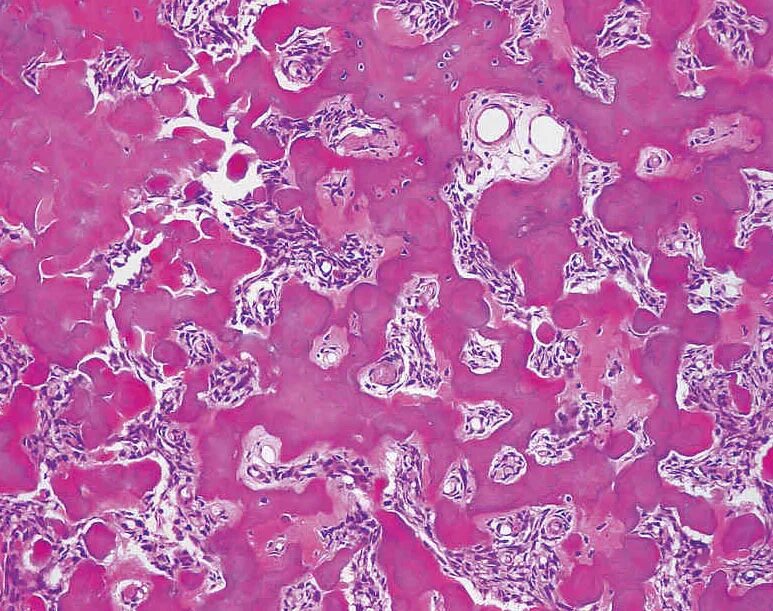

Патан пф